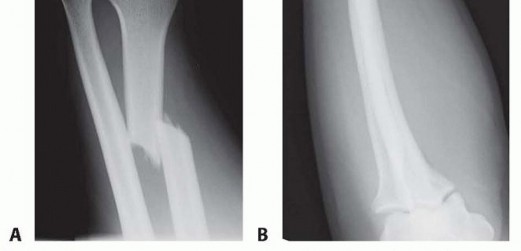

Fracture of the radial shaft with an associated distal radioulnar joint (DRUJ) dislocation ( FIG 1A,B)It is well established that anatomic stabilization of the radial shaft fracture typically results in a stable DRUJ that can be treated nonoperatively with a period of immobilization.When the DRUJ is either irreducible or unstable, following anatomic reduction and compression plating of the radius fracture, operative stabilization of the DRUJ is required.Pediatric injury is not discussed in this chapter.

FIG 1 • Classic Galeazzi injury. A. A distal-third radial shaft fracture with ulnar angulation of the distal fragment, radial shortening, and DRUJ widening. B. Apex dorsal angulation of radial shaft fracture with dorsal dislocation of ulnar head. Triangular fibrocartilage complex (TFCC)The dorsal and volar radioulnar ligaments of the TFCC are considered the primary stabilizers of the DRUJ. 18 The deep fibers of the radioulnar ligaments attached at the fovea are located at the base of the ulnar styloid.For this reason, in the less common instance when an ulnar styloid base fracture accompanies a Galeazzi fracture-dislocation, fixation of ulnar styloid fracture may restore DRUJ stability.Distal interosseous membrane (DIOM) and distal oblique bundle (DOB)The DIOM lies deep to the pronator quadratus and connects the radius and ulna ( FIG 2A).Biomechanical studies demonstrate that the distal membranous portion of the interosseous membrane functions as a secondary stabilizer of the DRUJ. 14,20When present, the DOB originates at the distal ulna and inserts at the inferior rim of the sigmoid notch of the radius blending with the capsular tissue of the DRUJ. 18 Cadaveric studies report the DOB is present in 40% of specimens (FIG 2B).15Moritomo 14 has hypothesized that in Galeazzi fracture-dislocations, when there is loosening but not rupture of the DOB, instability can be managed by anatomic reduction of the radius.Radius reduction and the subsequent retensioning of the DOB restore stability even when a TFCC injury ispresent. Persistent DRUJ instability after radial fracture restoration may be the result of DOB disruption. 14 RadiusThe majority of Galeazzi fracture-dislocations occurs in distal third of the radius but can occur anywhere along the radius. 12Greater than 50% of radial shaft fractures less than 7.5 cm from the distal radial articular surface are associated with injury to the DRUJ compared to 6% of more proximal radial shaft fractures. 17